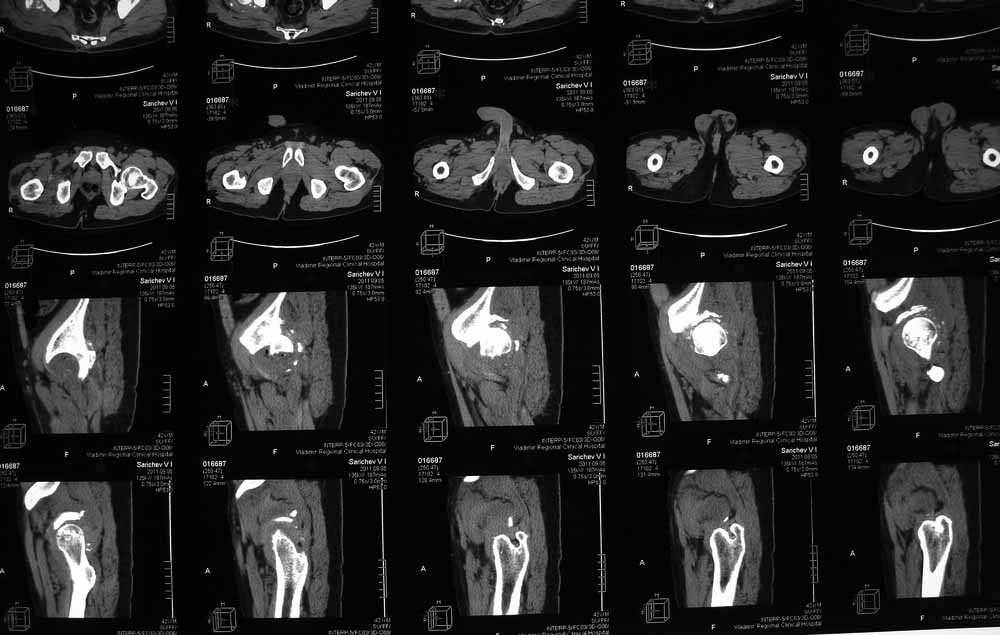

Re: Застарелый вывих бера, перелом вертлужнойвпадины, перелом головки бедра

Вот еще сканы.